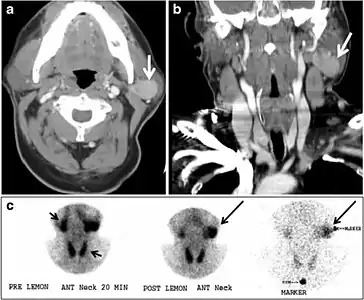

Fig. 8. A 48-year-old male patient post total thyroidectomy with PTC recurrence. a Transverse greyscale ultrasound of the neck demonstrates a left thyroid bed heterogeneous, predominantly hypoechoic irregular lesion with calcifications (white arrow). b A spot image of iodine 123 total body scan of the neck demonstrate a focus of abnormal radiotracer uptake at the left thyroid bed (Black arrows) between the annotated markers. c Enhanced axial CT scan of the neck demonstrates an enhancing large left thyroid bed mass (white arrow) with no calcifications. The lesion exerts a mass effect on the oesophagus (black arrow) and is inseparable from the trachea.[1]

Fig. 17. Ectopic thyroid on the left parotid gland with a palpable left parotid mass in a 69-year-old male patient. a, b Axial and coronal enhanced neck CT scan demonstrates well-defined homogeneous enhancing mass (white arrows) within the left parotid gland with preserved surrounding fat planes. It also shows a normal thyroid in normal position in the lower neck. c Image taken 20 minutes after 5 mCi injected Tc99m-Pertechnetate shows normal thyroid uptake of tracer and physiological uptake in the salivary glands (short black arrow). There is a distinct focus of abnormal tracer accumulation in the left parotid/submandibular region. Patient was given lemon juice with evident normal washout from the salivary glands and relative retention by this abnormal focus (long black arrow).[1]

Fig. 18. Lingular thyroid in a 33-year-old male who presented with oropharyngeal bleeding. an Axial enhanced neck CT scan at the level of mandible demonstrates a 3 × 3 × 3.4 cm round, partly well-delineated, heterogeneously enhancing lesion (white arrow). It is predominantly on the left side of the oropharynx and to some extent at the mid part of the base of the tongue. Thyroid gland was normal (not shown). b Image of the anterior face and neck taken 20 minutes after Tc99m-Pertechnetate injection shows absent thyroid radiotracer uptake in normal thyroid anatomical location (black short arrows). There is an area of increased uptake (long black arrows) corresponding to posterior tongue mass identified on CT scan.[1]